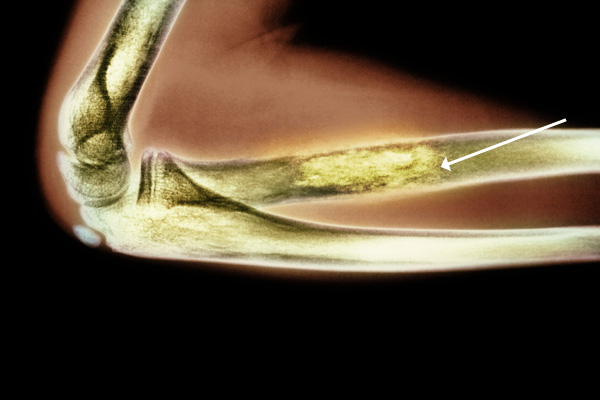

σάρκωμα EwingΧρωματιστή ακτινογραφία αγκώνα. Η καρκινική περιοχή τονίζεται με πιο έντονα κίτρινο χρώμα